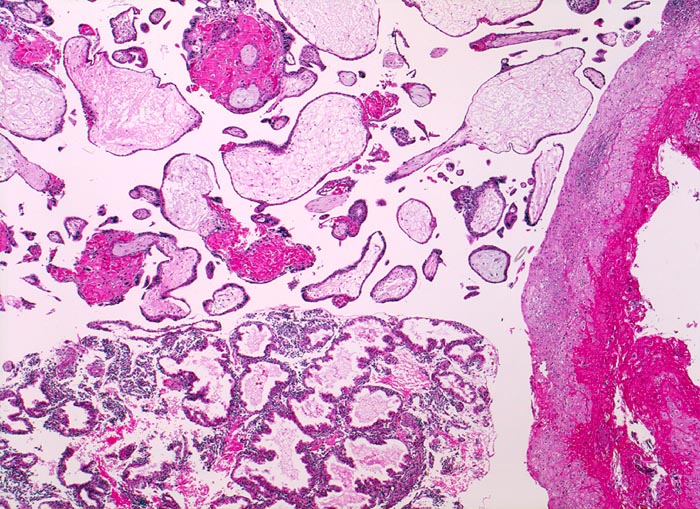

Schwangerschaftsendometrium mit hypersekretorischen Drüsen. Deziduafragment mit Einblutungen. Plazentarzotten mit Zeichen der Retention ( hydropisches Zottenstroma, Fibrinablagerungen).

Missed abortion in der 11. Schwangerschaftswoche, sonographisch entsprechend der 9. Schwangerschaftswoche.

Plumpe Zotten mit hydropischem Stroma ohne Gefässe und flaches Trophoblastepithel sind vereinbar mit einer Windmole (=Windei). Differentialdiagnostisch könnten die beobachteten Veränderungen auch retentionsbedingt sein.